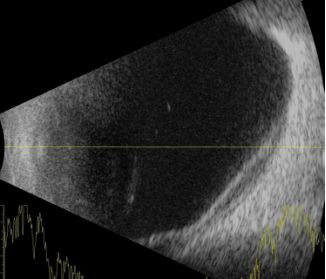

辅助检查:A超测眼轴长29mm,B超示左眼脉络膜多个球形隆起凸向玻璃体腔(图1)。

图1. 下方及颞侧可见弧形隆起均匀强回声